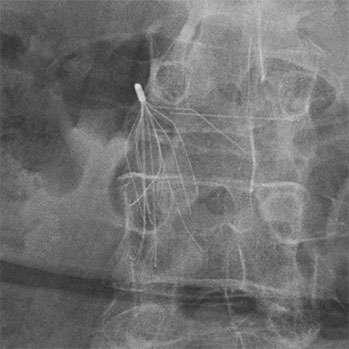

IVC Filter with fractured leg

The legs, also known as the ‘struts’, of the IVC filter can break off. These legs can then travel to other areas and may need to be removed. The areas the legs can move to include other blood vessels, the heart and lungs (migration).